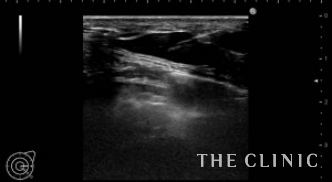

5年前にヒアルロン酸豊胸を受けられ、しこりになってしまったためしこり除去をご希望でご来院されました。ヒアルロン酸のしこりが大量にある場合は、しこり治療とCRF注入を同時に行うことにより脂肪壊死やしこりのリスクが高くなります。この方の場合は、少量のヒアルロン酸であったため、同時CRF注入を行いました。写真)エコー下にヒアルロニダーゼを注入します。

ヒアルロニダーゼがヒアルロン酸に混ざると、すぐに水様になるため吸引除去します。